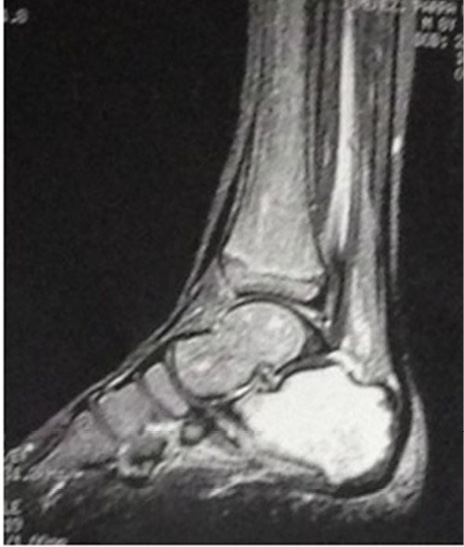

La radiografía convencional fue examen de rutina en todos los pacientes del estudio. Evidenció hallazgos inespecíficos en 5 de 9 pacientes consistentes en edema de tejidos blandos. En uno de esos casos se apreciaron lesiones óseas en el calcáneo (Figura 1). La TC se utilizó como complemento en un caso para confirmar un defecto óseo cortical secundario a la infección (Figura 2).

Figura 3. Resonancia del pie izquierdo del paciente de 8 años. Se nota un incremento en la intensidad en la secuencia de supresión de grasa en el calcáneo, compatible con cambios producidos por un proceso inflamatorio o infeccioso en este hueso. Imágenes propias de los autores